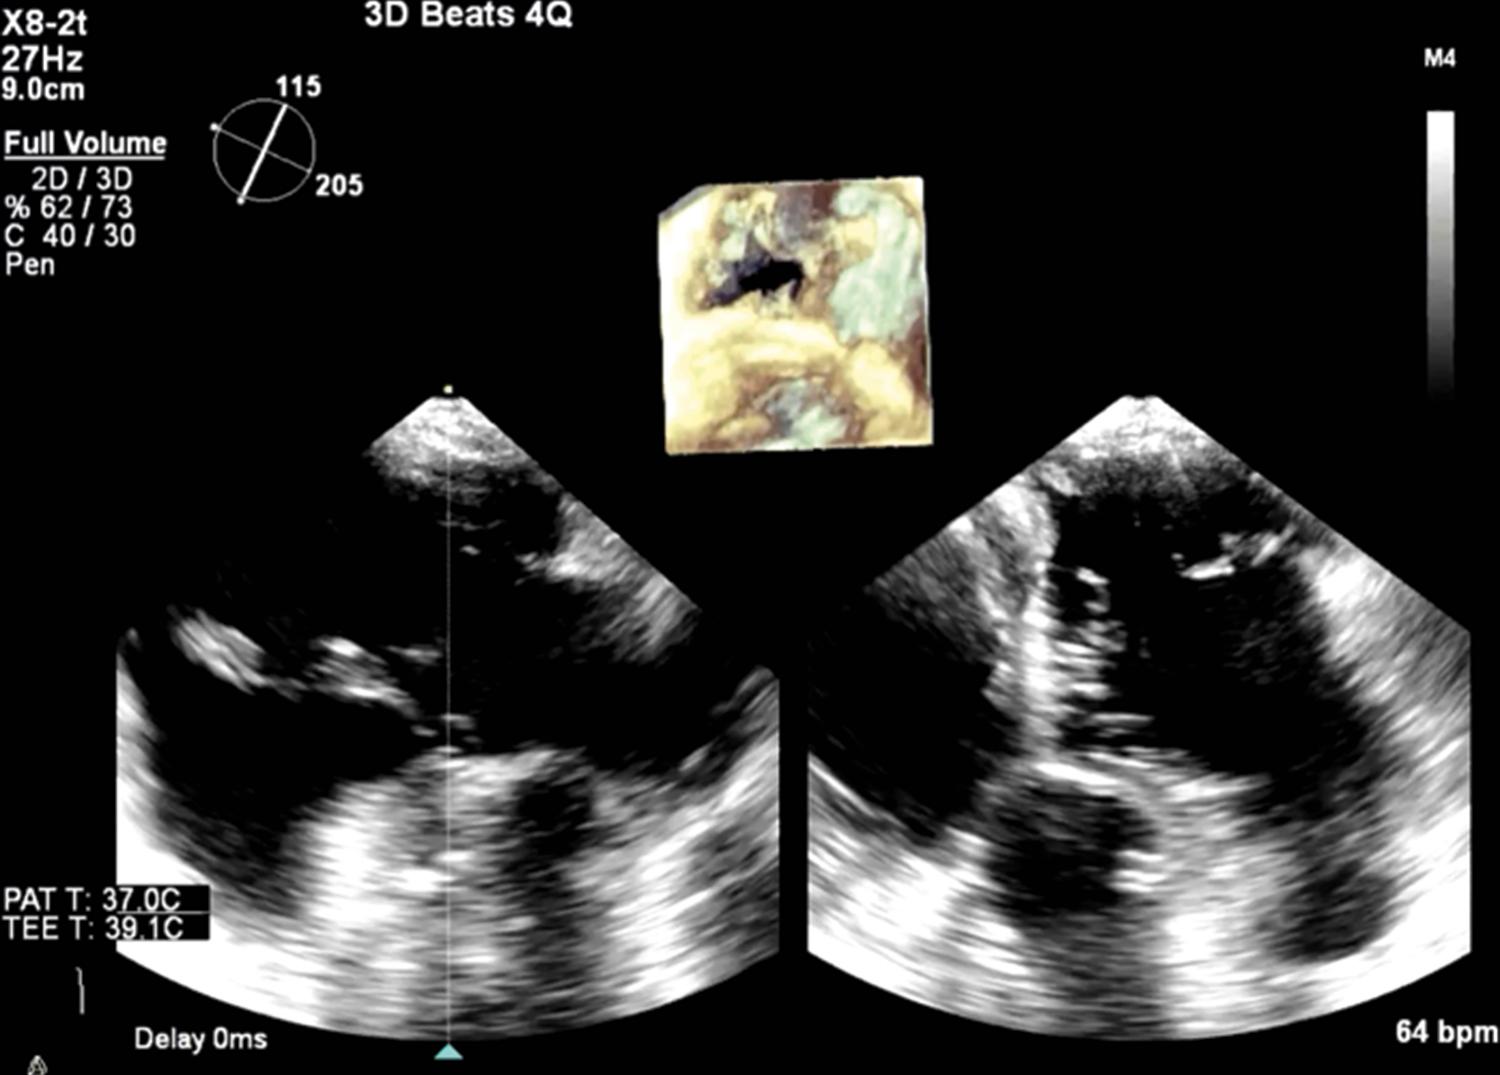

TEE is frequently used for the investigation of suspected or confirmed prosthetic valve dysfunction. Image quality of bioprosthetic and mechanical prosthesis is invariably enhanced by the use of TEE because of less acoustic shadowing and less obscuration of far-field structures. TEE is standardly performed for concern of prosthetic valve endocarditis because of its superior sensitivity and ability to evaluate for vegetation, abscess, or fistulous complications. With 2D and 3D TEE, careful delineation of prosthetic leaflet motion, degenerative changes, and the presence of pathologic thrombus, vegetations, or pannus can be performed, with consequential implications for clinical management ( Fig. 14.5 and , ). The introduction of 3D color imaging with adequate temporal resolution can also help to coregister abnormal regurgitant jets to the valvular or perivalvular space, as well as define the associated lesion severity ( Fig. 14.6 and ). Real-time TEE guidance is now standardly used for percutaneous valve interventions, including perivalvular leak closure.

Figure 14.5, A, Mechanical mitral prosthesis thrombosis with left atrial and valve-associated thrombus and dense spontaneous echo contrast in the left atrium. B, Mechanical mitral prosthesis dysfunction with immobile posterior mechanical leaflet on two- and three-dimensional imaging with pathology demonstrating amalgam of acute and chronic thrombus, with pannus formation ( C ). See accompanying Video 14.5A , Video 14.5B .

Video 14.5 . A, Two-dimensional imaging of a thrombosed mitral valve with dense spontaneous echo contrast layered in the LA. B, Three-dimensional en-face view of the same valve with evidence of stasis in the LA and abnormal leaflet mobility.